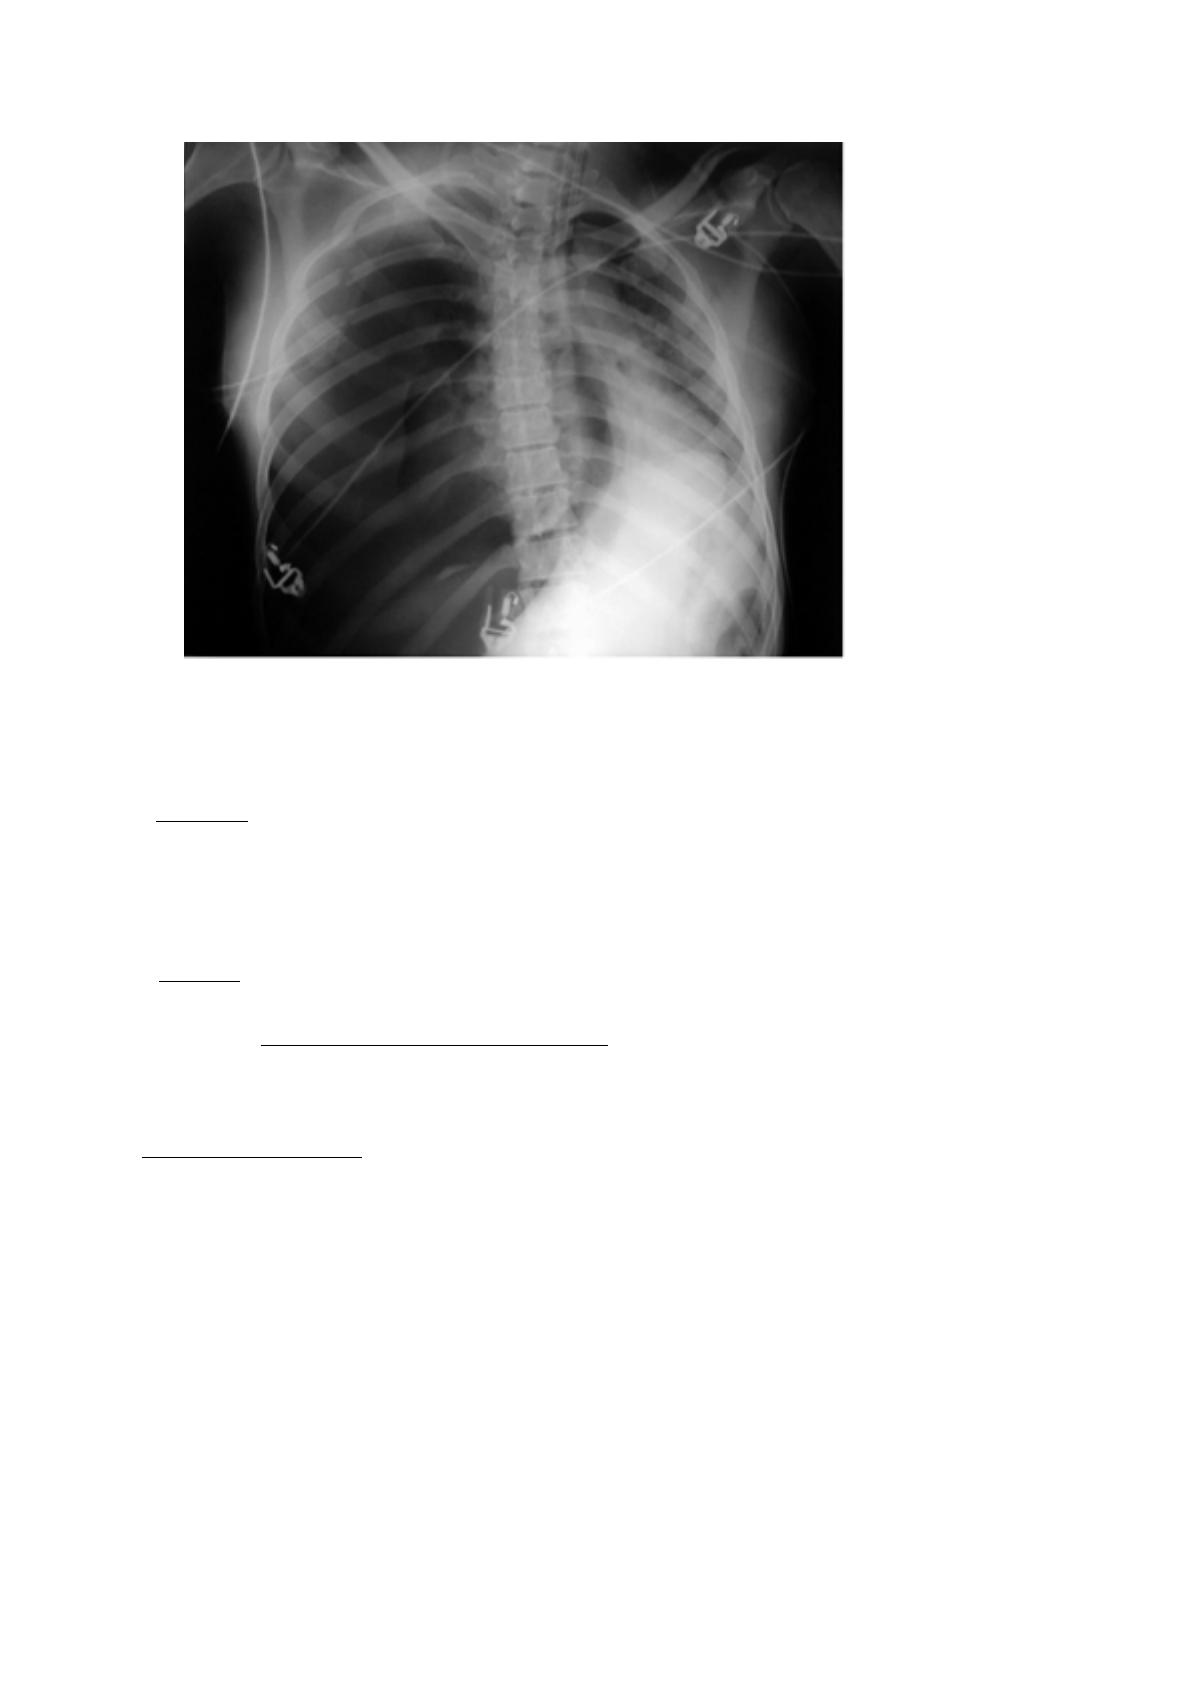

2) Application

1) Trachée

2) Clavicule droite

3) Cote

4) On voit mieux les corps vertébraux que le sternum à cause de leurs densités. Ici ce

n'est pas le sternum mais un organe : le coeur avec son oreillette droite.

5) Glande mammaire (sein dense donc femme jeune)

6) Estomac, avec sa poche à air gastrique sous coupole diaphragmatique gauche => ce

qui permet de dire qu’elle était debout.

7) Coupole diaphragmatique gauche

8) Cœur ventricule gauche

9) Artère pulmonaire

10)Aorte, si calcifiée : athérome formant une grosse boule blanche (à la radio) au niveau

de la crosse.

11) Champs pulmonaire ou bord interne de la scapula : ligne blanche à la verticale (d’où

la position lors d’une radio pour dégager les scapulas latéralement).

Pour analyser d’une radio, on regarde d’abord le contenant (cage thoracique :

sternum,cote,vertèbre) d’abord puis le contenu (poumons cœur)

- Contenant : sternum dans l’axe, fracture de cote (5), vertèbre avec une inclinaison gauche

donc pas debout, de plus pas de poche à air et patient intubé (deux traits blancs parallèles en

forme de biseau à la fin au niveau de la trachée) donc surement patient dans un coma

artificiel, allongé.

-Contenu : poumon gauche grisé avec des taches blanches = normal / le noir à droite sans

cloison pulmonaire = que de l’air : pneumothorax si important que le médiastin est refoulé à

gauche (= pneumothorax complet compressive refoulant le médiastin) / début de drain

pleurale mis pour diminuer le pneumothorax/ les fils blancs un peu partout, électrode du

scope sur la peau/ cœur comprimé par le pneumothorax.

Conclusion de la radio : fracture multi-focale thoracique droit avec pneumothorax compressif

refoulant le médiastin chez un patient intubé.